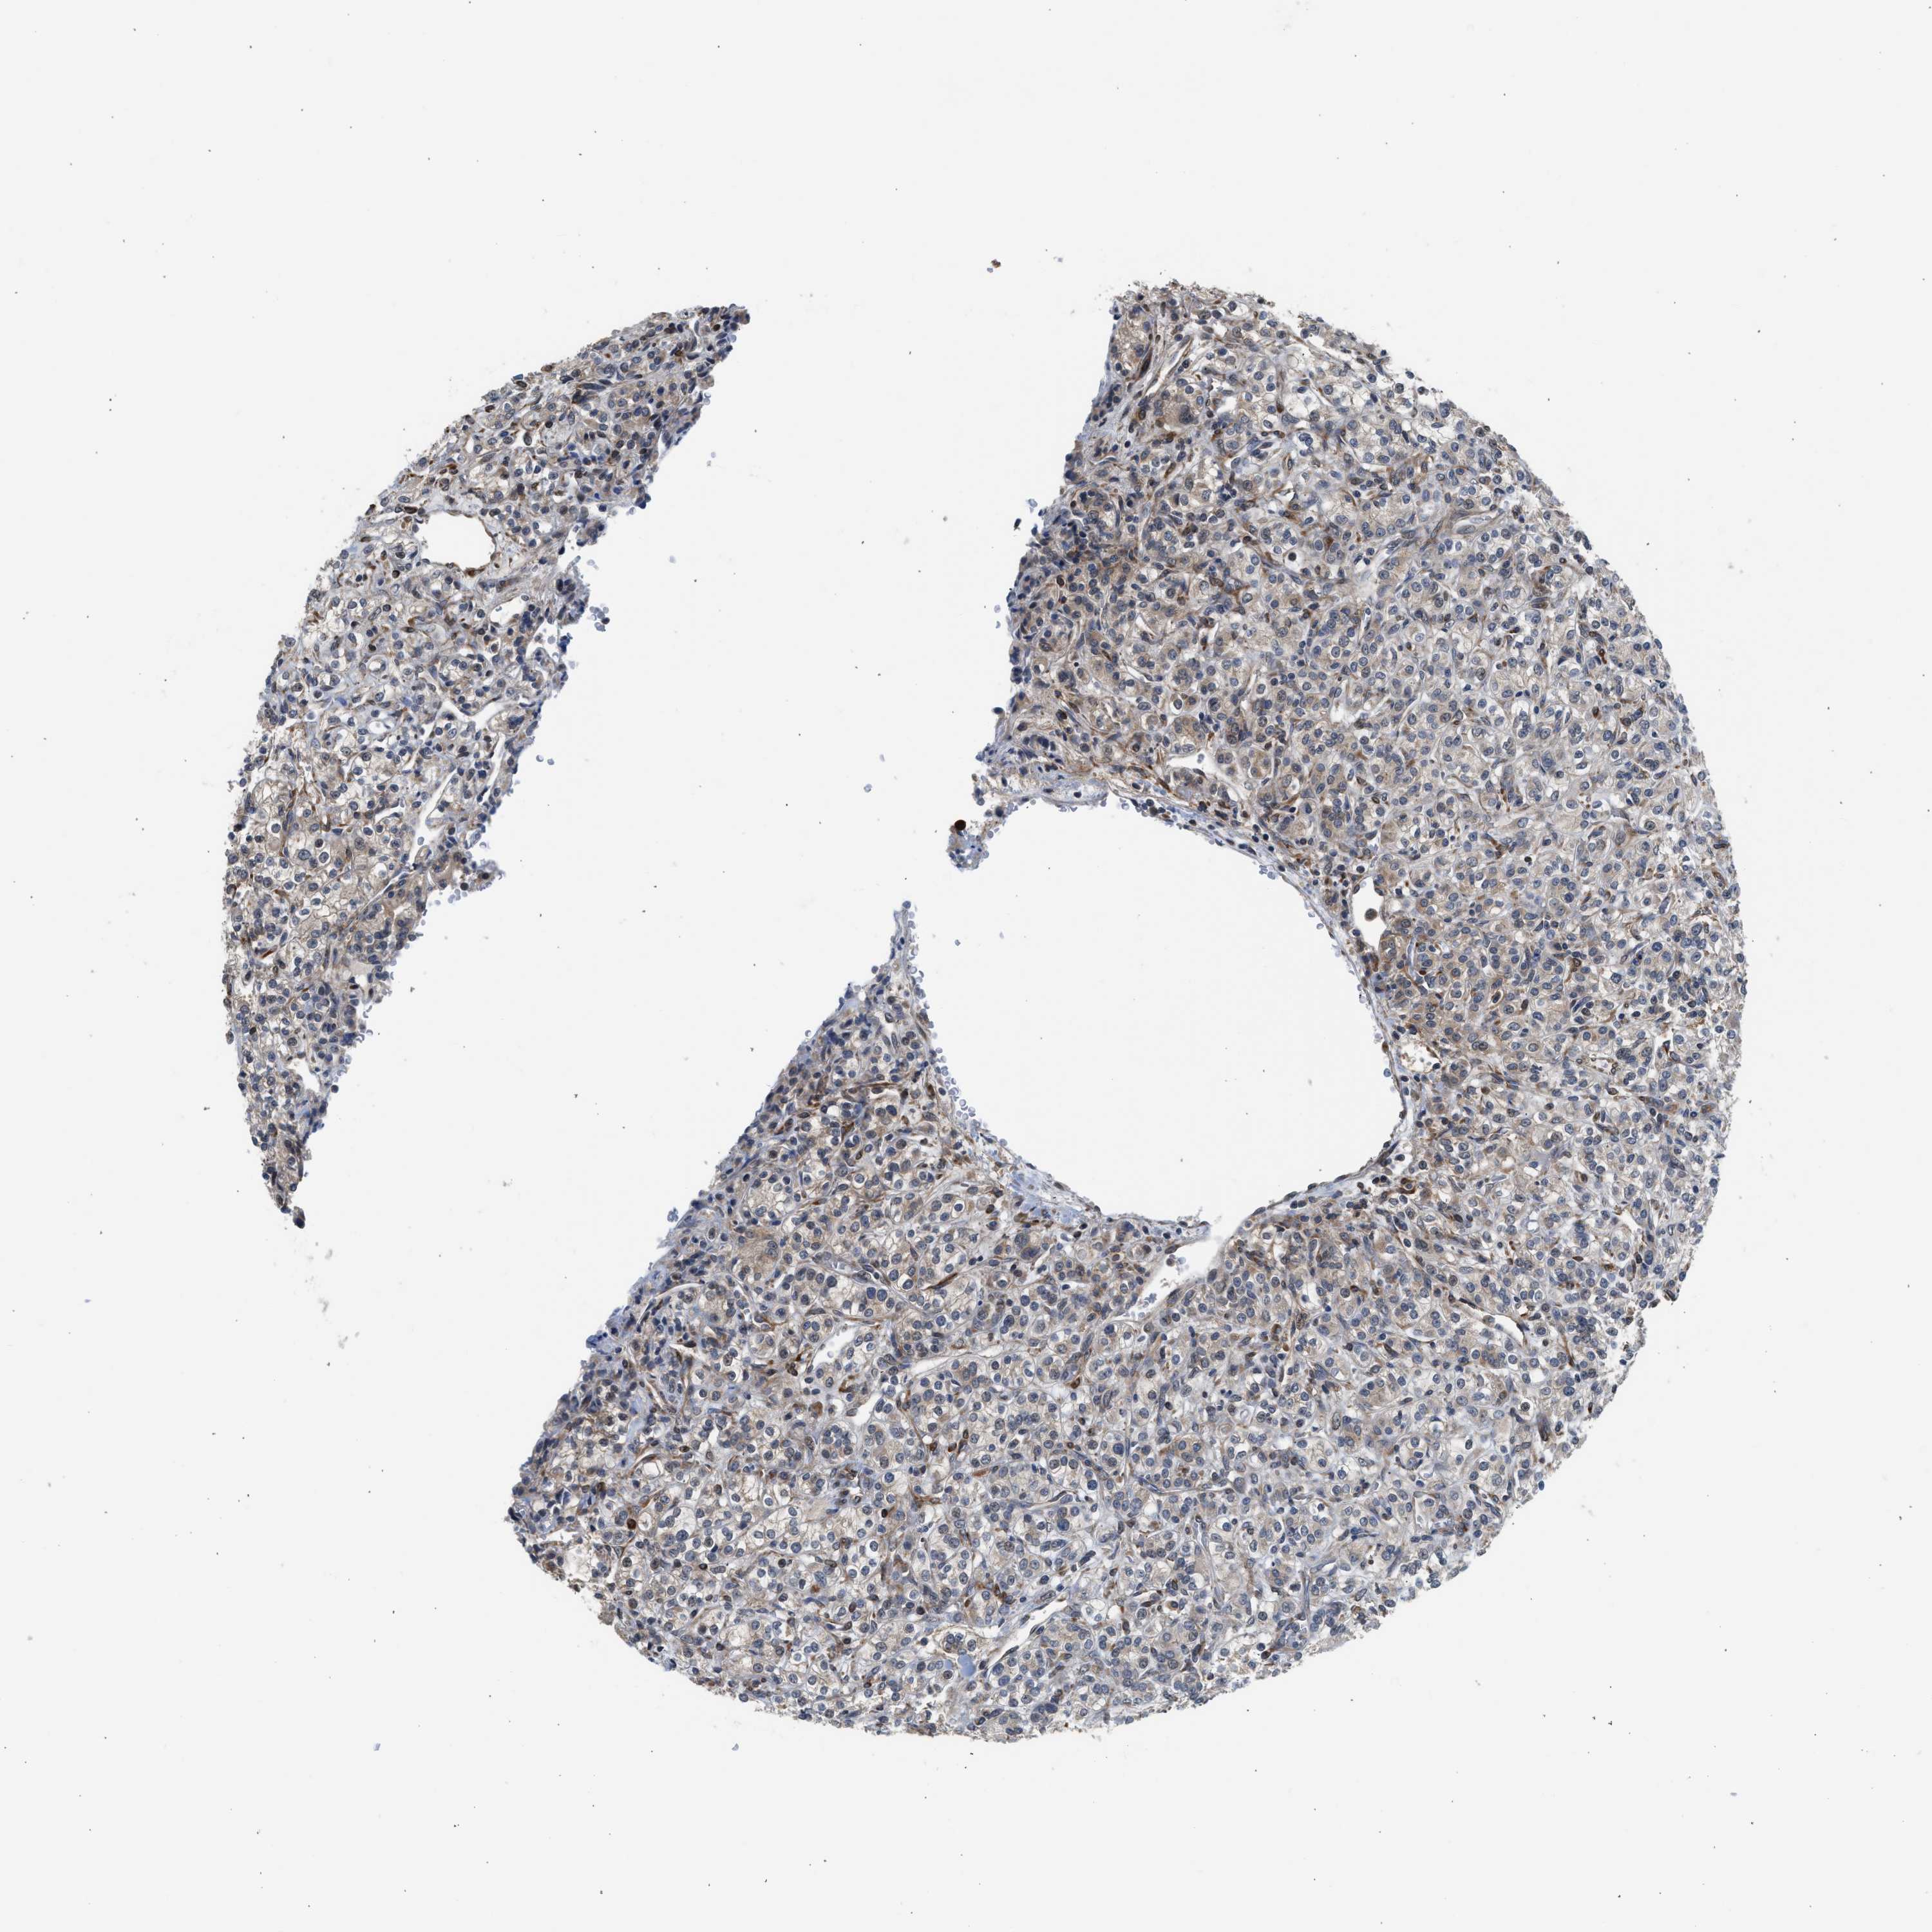

Renal cancer

Kidney renal clear cell carcinoma